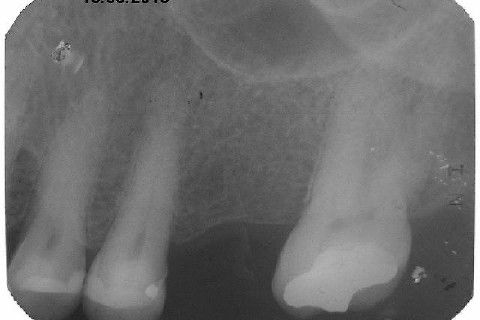

Instalação de um implante em região do 26. Utilizamos um implante cone morse Alvim Neodent 4.3 X 11,5. Foi uma cirurgia muito rápída e minimamente traumática, sem retalho e sutura.

Fotos do caso